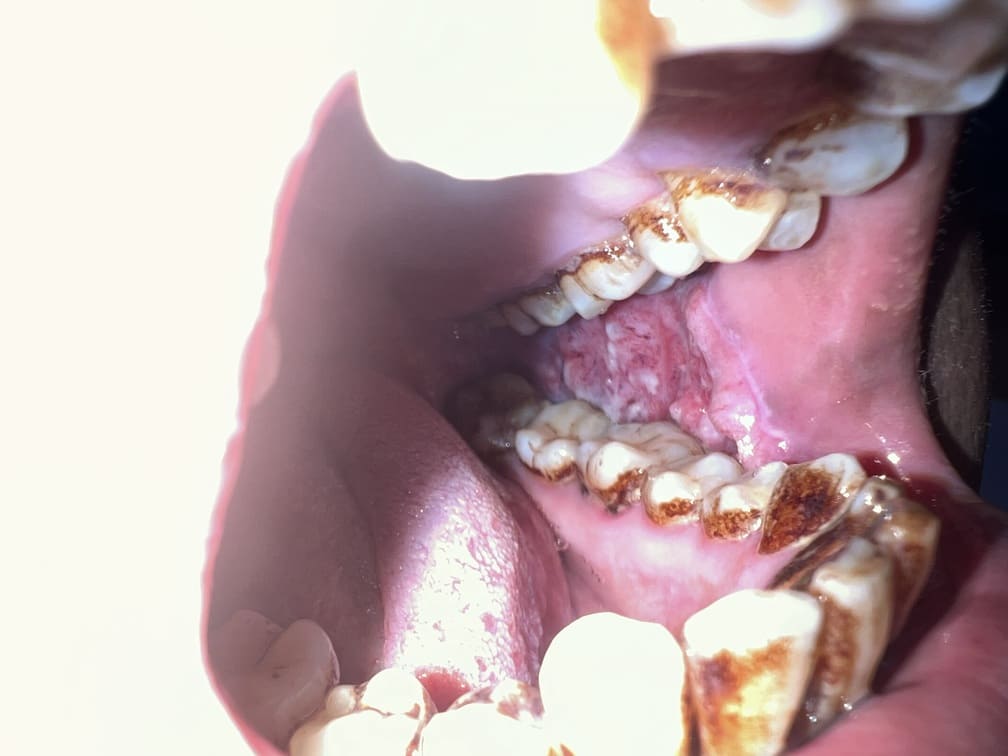

57 years old female suffering from left buccal mucosa growth involving left RNT and gingival surface of lip extending up to right angle mouth.left modified neck dissection with left distal segmental mandibulectomy with wide excision of left buccal mucosa with left RMT growth with excision gingival margin of lower lip with left pectoralis with right nasolabial flape done.

29-12-2025